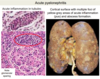

Which stain is used to view Chronic Glomerulonephritis?

What’s seen?

- Massone trichrome stain

- Showing complete replacement of all glomeruli by blue-staining collagen